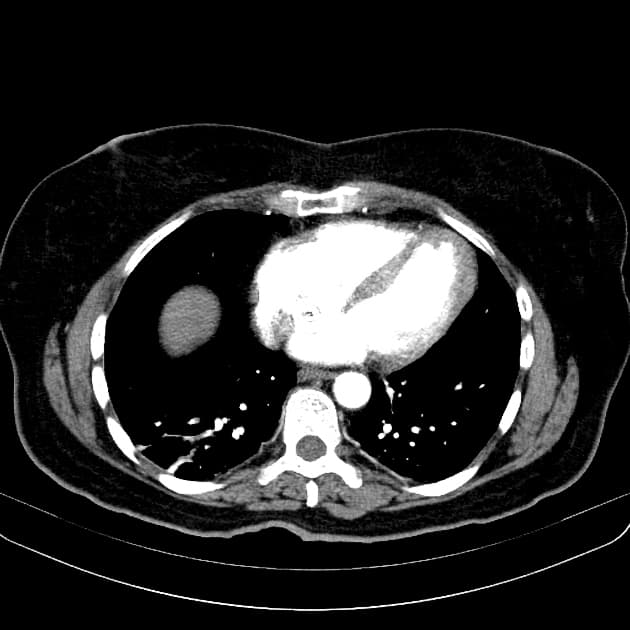

- Tổn thương dạng thùy (lobulated) kích thước 35 x 45 mm nằm ở phân đoạn V của thuỳ phải, liền kề với túi mật (gallbladder).

- Tổn thương này tăng tín hiệu (hyperintense) trên hình ảnh T2-weighted MRI.

- Trên hình ảnh cộng hưởng từ có tiêm thuốc tương phản động (dynamic contrast-enhanced imaging), thấy tăng quang dạng nốt (nodular) ở vùng ngoài viền (peripheral) ban đầu, tiếp theo là quá trình lấp đầy dần từ ngoài vào trong (slow centripetal filling).

Hình ảnh cộng hưởng từ (MRI) phù hợp điển hình với u sợi mạch gan (hepatic hemangioma).

- "U sợi mạch gan thường biểu hiện tăng tín hiệu T2 và tăng quang dạng nốt ở viền ngoài với quá trình lấp đầy từ từ từ ngoài vào trong trên cộng hưởng từ có tiêm thuốc tương phản động."

U sợi mạch gan là khối u gan lành tính phổ biến nhất, thường được phát hiện tình cờ trên hình ảnh học. Bệnh xuất phát từ các mạch máu bất thường và gồm các khoang giãn chứa đầy máu được lót bởi tế bào nội mô. Trên cộng hưởng từ (MRI), hình ảnh điển hình bao gồm tăng tín hiệu rõ rệt trên T2 và kiểu tăng quang dạng nốt ở vùng ngoại vi trong thì động mạch, tiếp theo là quá trình lấp đầy dần từ ngoài vào trong ở các thì muộn. Dấu ấn hình ảnh này rất đặc hiệu, cho phép chẩn đoán chắc chắn không xâm lấn trong hầu hết các trường hợp. Mặc dù có thể sinh thiết, nhưng thủ thuật này tiềm ẩn nguy cơ chảy máu và thường được tránh. Điều trị mang tính bảo tồn, không cần cắt bỏ hay theo dõi định kỳ trong các trường hợp điển hình, trừ khi có nghi ngờ chẩn đoán hoặc bệnh nhân có triệu chứng.